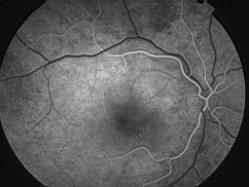

IM000006.jpg